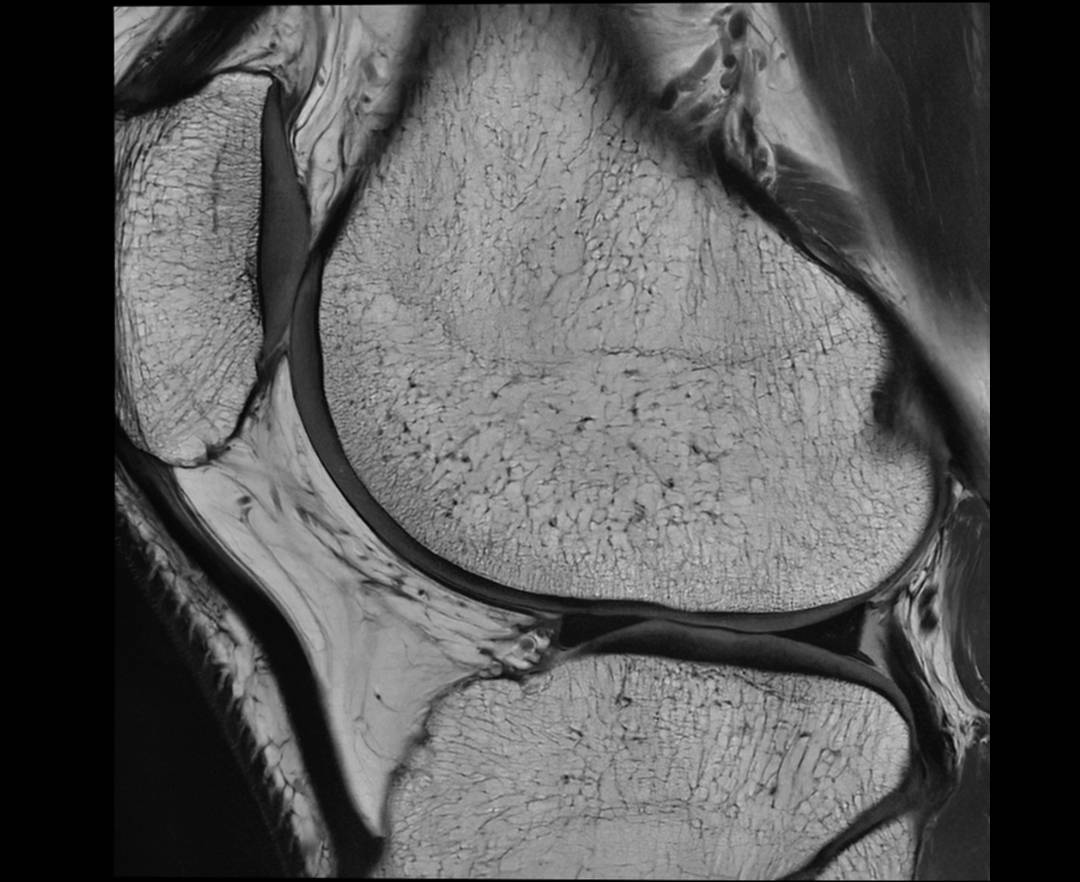

KNEE PD SAG

KNEE PD TRA